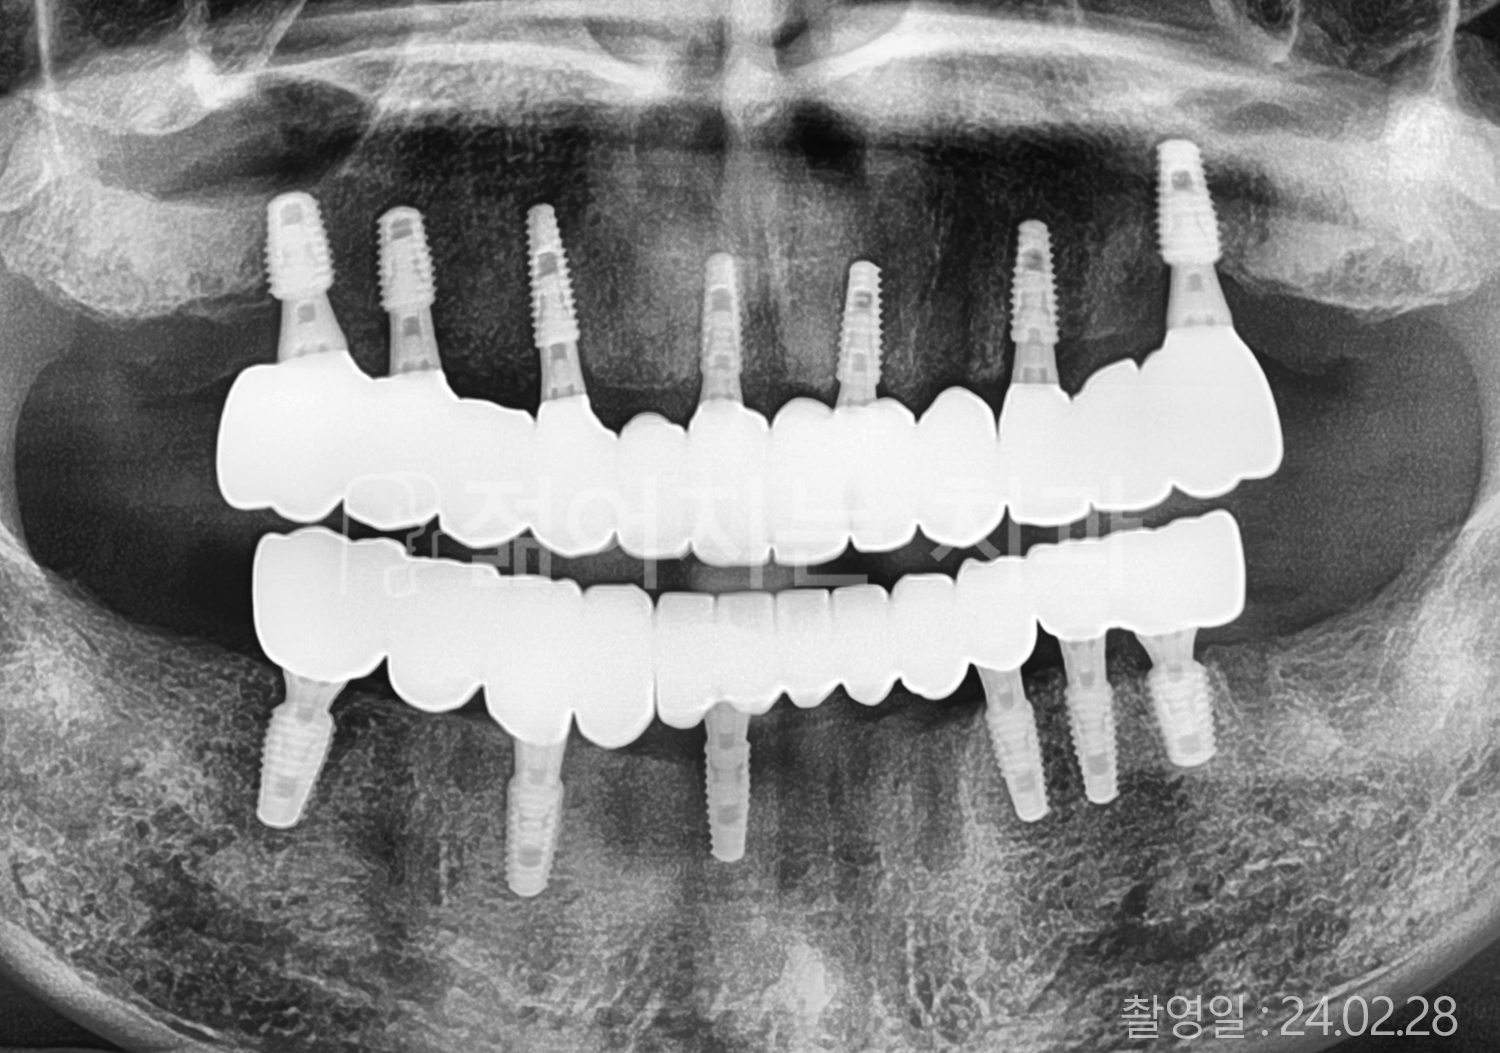

• 60대 전체치아 10개 이상 임플란트